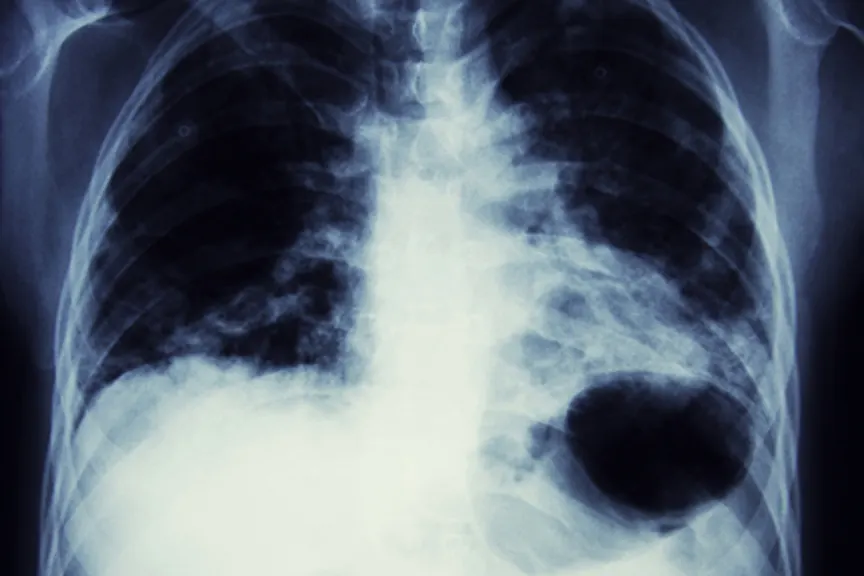

Typically a person presents with a past history or symptoms that warrant investigation with a chest x-ray. The chest x-ray is read as “abnormal” by the radiologist, who then usually states that a mass cannot be ruled out.

第一步是计算机断层扫描(CT)can of the chest. The purpose of the CT scan is to:

确认这确实这是一个坚实的质量,而不是气道或肺炎的融合。

衡量质量是多大的,识别其特征:平滑边界,不规则,推测等。其中一些特征将增加这是恶性肿块的可能性。

评估是否存在这种质量的延伸,仅仅是肺部的一个叶片,或者如果肺部外部延伸。

评估是否存在淋巴结显示出来。这将对癌症的扩散或转移产生影响。